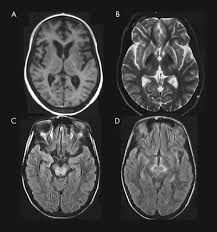

Wilson disease mri brain. MRI studies have identified focal abnormalities in the white matter pons and deep. Positive findings believed secondary to this condition were found in 15 subjects. Wilson disease hepatolenticular degeneration is an autosomal recessive defect in cellular copper transport.

6 8 Neurologic WD is one of the main forms of the disease. In Wilson disease WD T2T2weighted T2w MRI frequently shows hypointensity in the basal ganglia that is suggestive of paramagnetic deposits. It is currently unknown whether this hypointensity is related to copper or iron deposition.

Wilsons disease is an inherited disorder in which defective biliary excretion of copper leads to its accumulation particularly in the liver and brain. The patients were scanned using spin-echo SE sequences. Wilsons disease WD is due to excessive copper accumulation in the liver and brain 1.

The neurologist was looking for typical symptoms. Wilson disease also known as hepatolenticular degeneration is a multisystem disease due to abnormal accumulation of copper. It is characterized by early onset liver cirrhosis with CNS findings most frequently affecting the basal ganglia and midbrain.

The National Organizations for Rare Disorders NORD reported that 1 in every 30000 to 40000 people in the world are affected by WD 1. To describe the spectrum of brain abnormalities in Wilson disease hepatolenticular degeneration as depicted at magnetic resonance MR imaging and computed tomography CT and to relate these findings to neurologic and hepatologic abnormalities. 3 5 WD leads to intracellular copper accumulation causing damage to many organs especially the brain. Dysarthria tremor ataxia rigiditybradykinesia and choreadystonia. In Wilson disease WD T2T2weighted T2w MRI frequently shows hypointensity in the basal ganglia that is suggestive of paramagnetic deposits. Wilson disease also known as hepatolenticular degeneration is a multisystem disease due to abnormal accumulation of copper. It is found worldwide with a prevalence of approximately 1 case in 30000 live births in most populations. Patients neurological symptoms brain MRI features and laboratory findings were noted. The patients were scanned using spin-echo SE sequences.